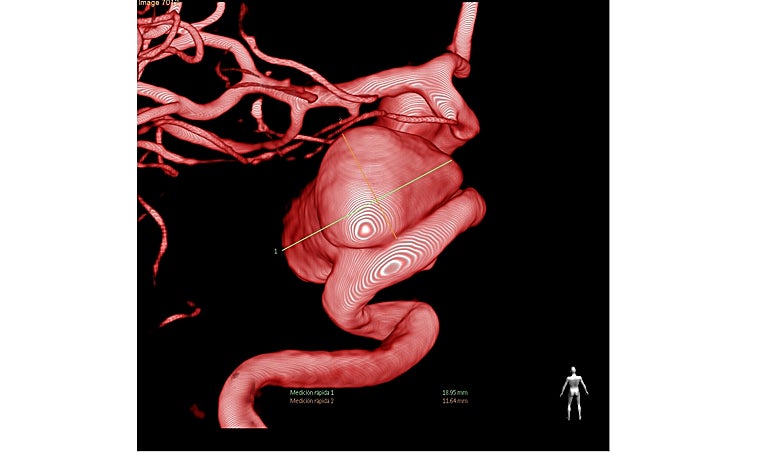

Se trataba de una paciente de 62 años con un aneurisma cerebral congénito con riesgo de sangrado en el que era precisa la implantación de un stent diversor de flujo para conseguir un cierre eficaz y seguro de la lesión. Según el doctor José Carlos Méndez, estas lesiones pueden asociar hasta un 10% de riesgo anual de hemorragia cerebral si no se detectan y se tratan a tiempo. «El tratamiento se realizó hace pocos días con el novedoso equipo de angiografía biplano instalado en el área quirúrgica del hospital», subraya el doctor.

En el caso concreto de esta paciente, tal y como explica el doctor Méndez, «era necesario disponer de la tecnología de imagen más avanzada para visualizar adecuadamente en 3D la lesión cerebral, debido a su complejidad anatómica». «Estos stents permiten el tratamiento del aneurisma sin manipular el mismo, ya que se implantan en la arteria donde asienta la lesión y condicionan cambio de flujo y trombosis del aneurisma, lo que minimiza los riesgos de la intervención», señala el doctor Vega.